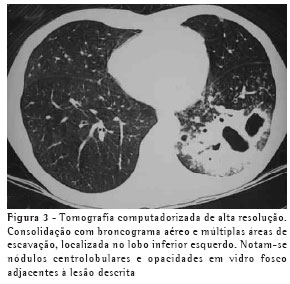

RESULTADOSO achado de imagem mais freqüente, presente nos 7 pacientes, foi consolidação de contornos mal definidos (Figuras 1, 2, 3 e 4), sendo que 5 deles tinham broncograma aéreo de permeio, principalmente na periferia da lesão. Em 3 casos, a consolidação organizava-se sob forma de massa. Em 6 dos 7 pacientes foram observadas, no interior das consolidações, áreas irregulares de escavação, múltiplas em 5 e única em 1 paciente. Em um dos casos não se observou escavação, mas ele mostrava áreas hipodensas de permeio, sugestivas de necrose (Figura 5). Apenas um dos pacientes apresentou nível líquido no interior das cavidades.

A lesão escavada predominou nos lobos superiores, sendo 4 à direita e 1 à esquerda. Em um destes pacientes, ela acometia também o lobo médio. Em 2 casos, ela ocorreu nos lobos inferiores, 1 à direita e 1 à esquerda. Em 4 casos as lesões acometiam apenas os lobos citados, sendo portanto unilaterais. Nos outros 3, atingiam também, em menor intensidade, o pulmão contralateral. Em um caso, havia também escavação de paredes relativamente finas, multisseptada, sem nível líquido, localizada no lobo médio.

Opacidades em vidro fosco foram vistas em 6 pacientes, localizadas predominantemente ao redor das lesões escavadas, não sendo, em nenhum dos casos, achado predominante.

Pequenas opacidades nodulares centrolobulares e padrão de árvore em brotamento foram vistos em 3 pacientes, com distribuição predominantemente ao redor da área de consolidação. Em 1 destes pacientes estas lesões foram encontradas também nas porções pendentes dos lobos inferiores. Nódulos do espaço aéreo, tendendo a confluência, localizados na periferia das consolidações pulmonares, foram vistos em 4 casos.

Na nossa casuística, o principal padrão de acometimento pulmonar foi o de consolidação com broncograma aéreo de permeio e escavação, presente em 6 pacientes, sendo as escavações múltiplas em 5 casos e única em 1. As consolidações tinham grandes proporções e contornos anfractuosos. Os broncogramas aéreos estavam localizados nas porções periféricas das lesões. O lobo pulmonar mais freqüentemente envolvido foi o lobo superior direito, acometido em 4 pacientes. A maioria dos trabalhos de revisão de casos confirma tais achados.(2,5) Alguns trabalhos relatam que, embora a escavação possa não estar presente no momento do diagnóstico, ela acaba por se desenvolver durante a evolução da doença.(4) Níveis líquidos no interior das escavações foram vistos em apenas um paciente na casuística estudada.

Outros achados foram as opacidades em vidro fosco, os nódulos do espaço aéreo, os pequenos nódulos de distribuição predominantemente centrolobular, e o padrão de árvore em brotamento. Eles se localizavam predominantemente ao redor das consolidações escavadas, sendo que em um dos casos também estavam presentes em ambos os lobos inferiores. Acredita-se que tal achado deva representar disseminação broncogênica da infecção.